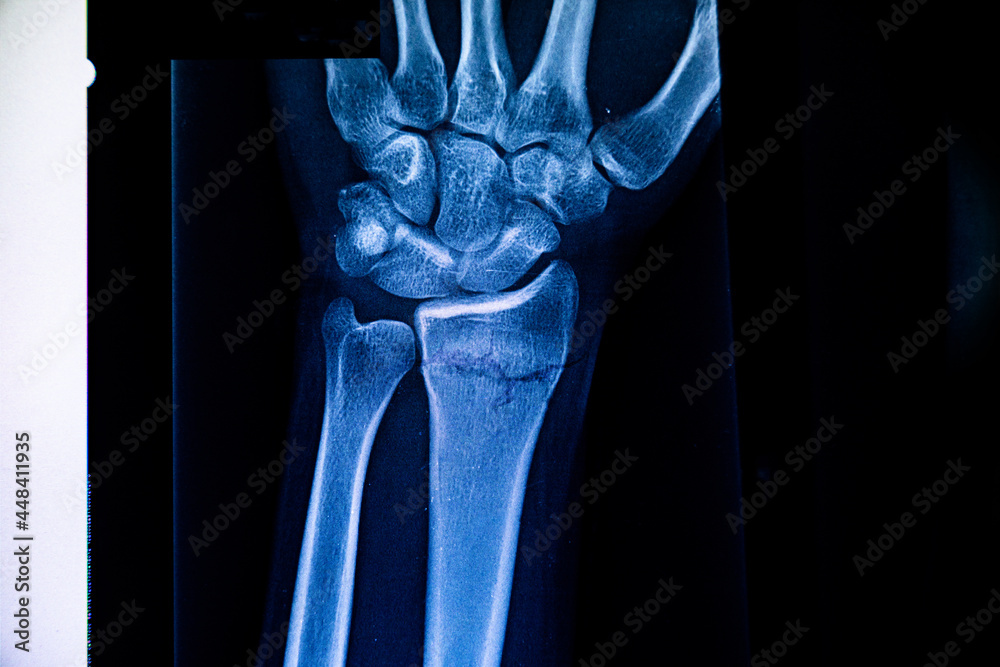

Xray of a wrist with a distal radius fracture that has healed in

From stock.adobe.com

Radiography examination of radius fracture. Xray human arm. Xray of Radius Xray Anatomy The radius and ulna form an anatomical unit, joined throughout their length by an interosseous ligament and stabilised at the elbow and wrist, thus forming a ring. Summarize the treatment options for distal. If there is a fracture of the. It lies laterally and parallel to ulna, the second of the forearm bones. The radius pivots around the ulna to. Radius Xray Anatomy.